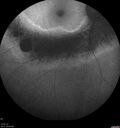

Sectoral Retinitis Pigmentosa - Asymptomatic253 views56-year-old female - The patient was in for an annual checkup because of her diabetes. No visual complaints (no night vision trouble)

293 Invitae genetic panel - negative     (0 votes)